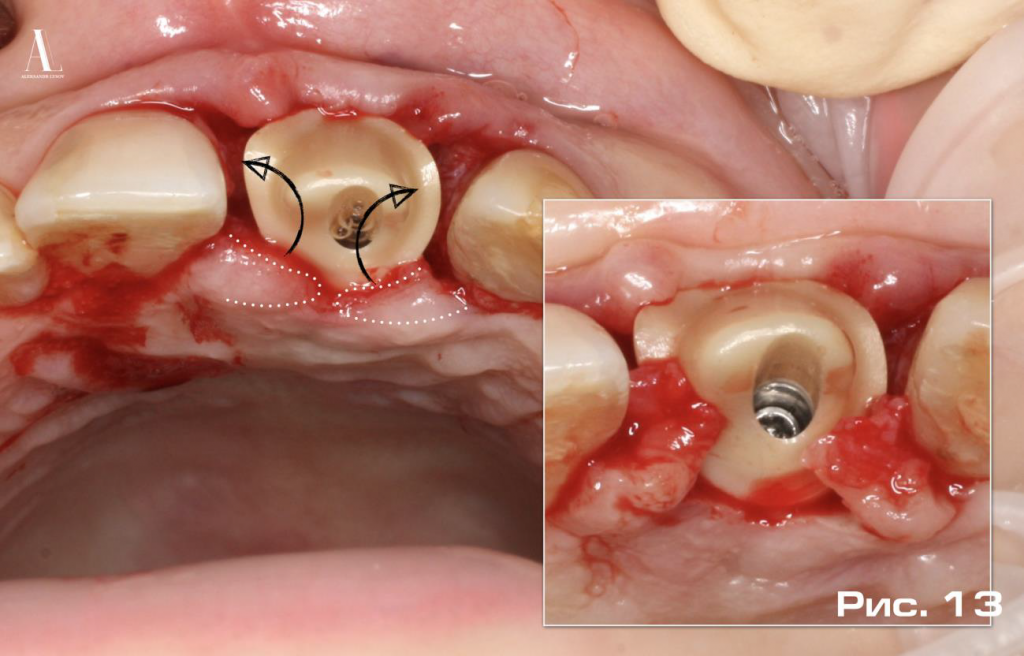

Полученный избыточный объем мягких тканей небного мукопериостального лоскута был использован для создания апрксимальных десневых сосочков, при этом применялась модифицированная методика ротированных лоскутов, предложенная Pallaci P et al. в 1995 году (Рис. 13).